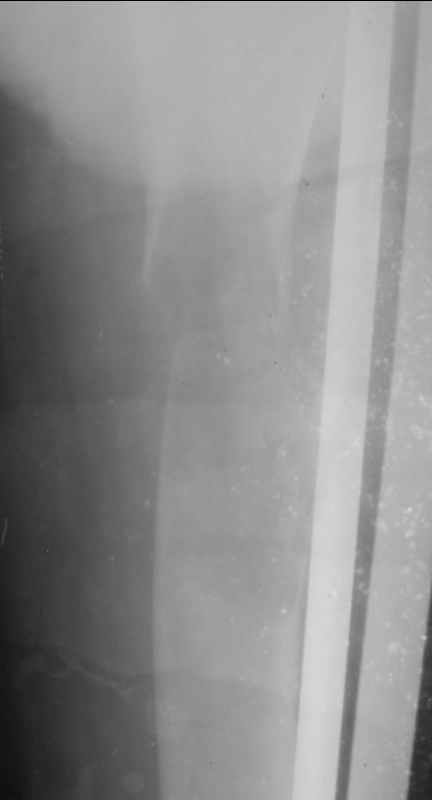

На мой взгляд, рентгенологическая картина все же напоминает солитарную кисту. В похожей ситуации мы выполнили (на фоне патологического перелома) васкуляризованную аутопластику малоберцовой костью на сосудистых анастомозах. Наблюдаем уже более 2 лет. Нагрузка на конечность в полном объеме, боли отсутствуют (рентгенограмма в аттачменте).

05070001.jpg